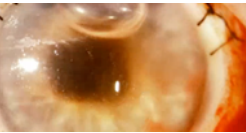

Cataracts

Abnormal Finding for 10. Inspect the cornea and lens

Opacities of the lens

Nuclear Cataract

Peripheral Cataract

Nuclear Cataract

One of the 4 Lens Abnormalities

Appear gray when seen with a flashlight

Appear as a black spot against the red reflex when seen through an opthalmoscope

Peripheral Cataract

One of the 4 Lens Abnormalities

Looks like gray spokes that point inward when seen with a flashlight

Look like black spokes that point inward against the red reflex when seen through an opthalmoscope